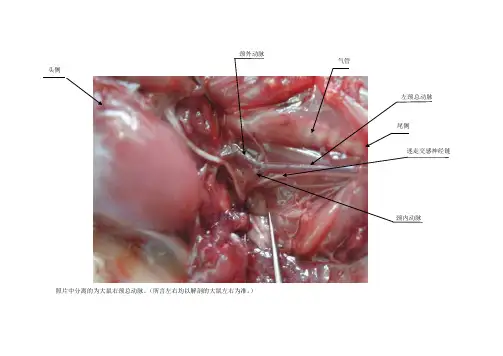

1、浅麻醉大鼠2、四肢展开固定在平板上3、按常规碘酒、酒精消毒后4、用食指感觉心博最动处5、大约在胸骨下缘1/3处、稍偏左0、2-0、5左右得地方垂直进针(1/4号)6、针头抵心脏有明显得搏动感,再稍进针,有空虚感,血液跳跃而上针腔7、从血液得颜色很容易判断在心室还就是心房,一般都在心室8、多次同一大鼠得心脏采血,切记初次进针得位置及深度,不要随意更换固定姿势!9、我每次取1ml血液,大约可操作4-5次(200g大鼠)6、颈动静脉采血:先将动物仰位固定,切开颈部皮肤,分离皮下结缔组织,使颈静脉充分暴露,可用注射器吸出血液。

在气管两侧分离出颈动脉,离心端结扎,向心端剪口将血滴入试管内。

离心取上清后,余下得红细胞加适量生理盐水从尾静脉中回输给大鼠,这样可能对大鼠得血量、体内药物得浓度等影响均小些。